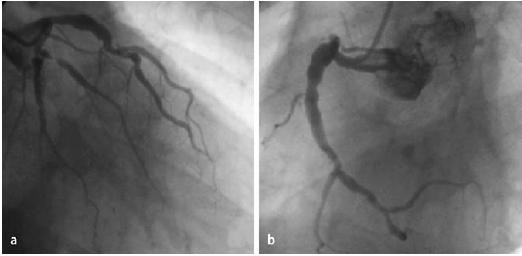

Coronary angiogram showing ectasia affecting the proximal portion of the left anterior descending coronary artery (a) and right coronary artery (b) of the same patient